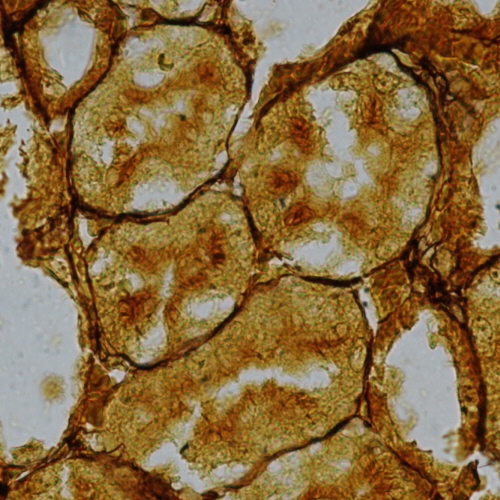

Reticular fibres (reticulin), thin fibrils of type III collagen, form a loose mesh in many support tissue and are particularly prominent just below the basement membrane. They form a network to support the cells in parenchymal organs like the liver and kidney.